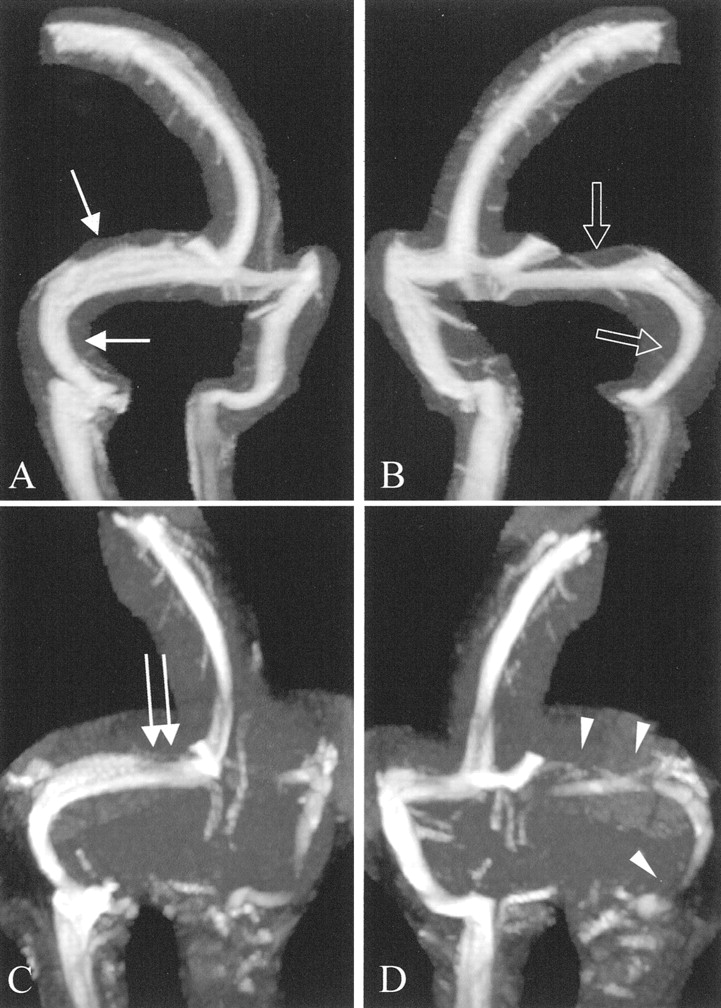

图6。ATECO vs TOF MRV。(一)老挝和(B)拉奥分段最大强度投影(MIPs) ATECO MRV的控制病人展示良好的可视化的右(箭头)和左(打开箭头)横向和乙状窦。注意缺乏artifactual信号损失。(C和D)相应oblique-segmented MIPs从TOF MRV在同一病人获得先生在同一考试。注意信号的大量artifactual损失近端右横窦(弯曲的箭头)和最左横窦(箭头)。